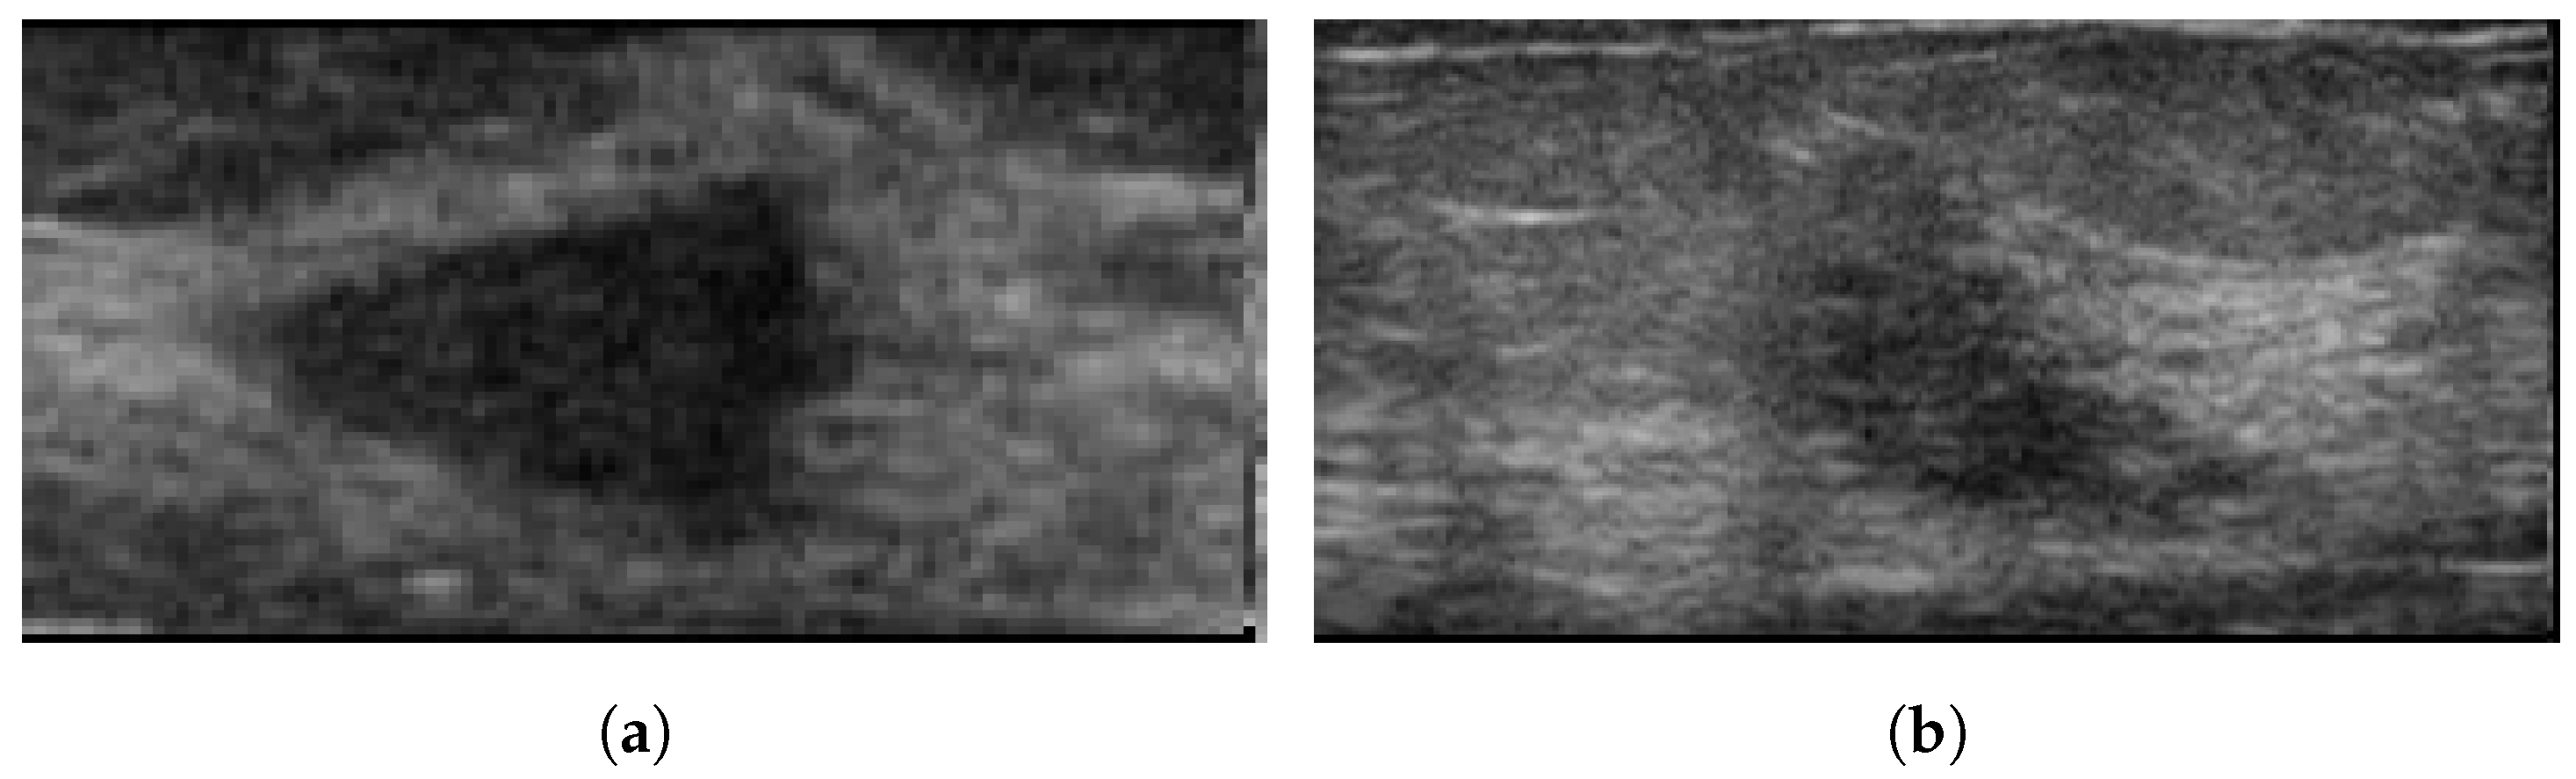

3.10. Breast Ultrasound Image

Breast Ultrasound Image (BUS) [50], collected in 2017, is a publicly available Mendeley dataset. The dataset consists of 250 breast cancer images, of which 100 are benign and 150 are malignant. The size of the images are 72 × 72 pixels, ranging in width from 57 to 61 pixels and height from 75 to 199 pixels [51]. These images are available in BMP format. It has been widely used in various studies [52,53,54]. Figure 5 illustrates some sample images from the Breast Ultrasound Image (BUS) dataset.